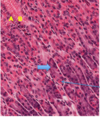

·So blood is flowing toward the central vein (i.e. toward the black star shape), whereas the bile, which is begin formed in these bile canaliculi, here indicated sort of diagrammatically as this green stuff, flows toward the portal tract.

·So the secretion of bile into ducts is an exocrine function, and the secretion of albumin, lipoproteins, IgF1 in response to growth hormones – things like that into the blood are going to be the endocrine functions of the liver, and – as this points out – blood and bile flow in opposite directions in the lobules of the liver.

2: bile duct

3: hepatic arteriole

4/7: portal venule